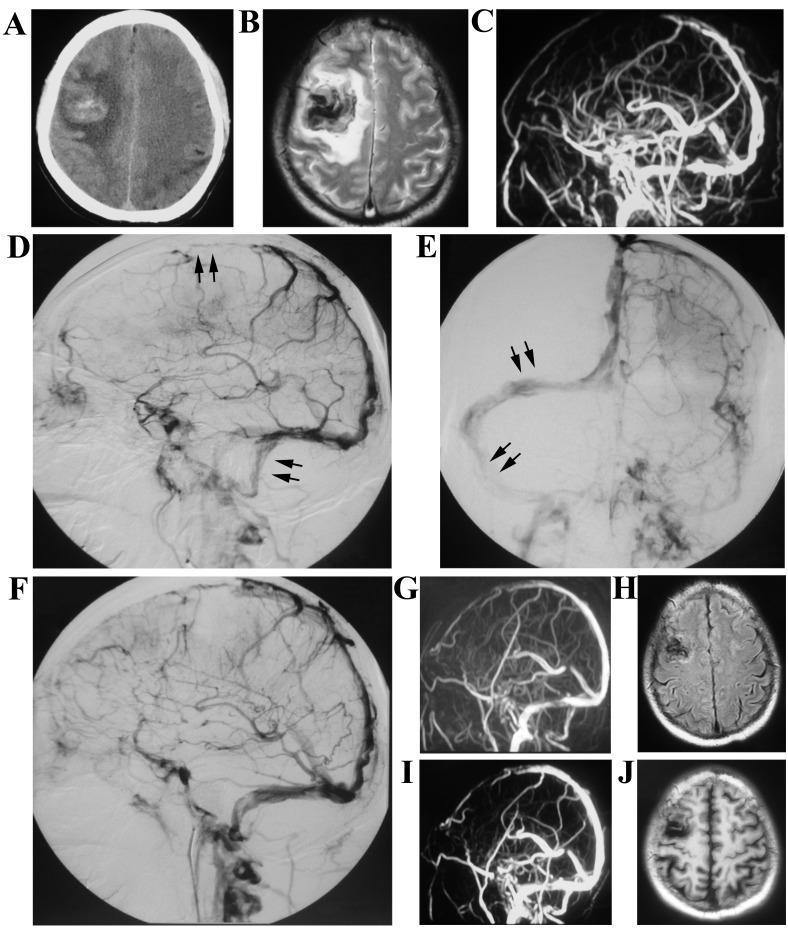

The present study reports the effect of successful treatment of cerebral venous sinus thrombosis (CVST) with stent retriever thrombectomy combined with local thrombolytic therapy. Medical records of 29 patients were retrospectively analyzed following a diagnosis of CVST with magnetic resonance venography (MRV) or digital subtraction angiography (DSA). Systemic anticoagulation was the initial treatment in all patients following admission. In group A, stent retriever thrombectomy combined with local thrombolytic therapy was performed on 14 patients who met the criteria of endovascular therapy. Stent-assisted angioplasty was also performed when patients presented with venous sinus stenosis. A total of 15 patients in group B received systemic anticoagulant treatment. Subsequently, warfarin was administered orally for 3 to 12 months as a continuous anticoagulant therapy. International normalized ratio was monitored when patients were receiving anticoagulant therapy. Additionally, clinical presentation, decision to escalate therapy, recanalization, Glasgow Coma Scale, modified Rankin Scale (mRS) and the clinical outcome was assessed. A total of 14 patients (9 female patients, 5 male patients), with ages ranging from 17 to 57 years, met the criteria of endovascular therapy. The clinical symptoms of 12 patients had improved after receiving endovascular therapy and only 2 patients suffered from intracranial hemorrhage following the procedure. Complete recanalization of venous sinus was exhibited in 10/14 (71.4%) patients in group A when compared with 1/15 (6.7%) patients in group B. mRS were improved in the 12-month follow-up in groups A and B when compared with that at admission. In the present study, patients with acute CVST treated with stent retriever thrombectomy combined with local thrombolytic therapy had a favorable outcome. To conclude, the present study provides a treatment option in treating CVST, particularly for patients that present with evident cortical venous outflow stasis or deteriorate neurology, despite appropriate anticoagulant therapy.

本研究报告了采用支架取栓联合局部溶栓治疗脑静脉窦血栓形成(CVST)的疗效。对29例经磁共振静脉血管造影(MRV)或数字减影血管造影(DSA)诊断为CVST的患者病历进行回顾性分析。所有患者入院后均首先进行全身抗凝治疗。A组中,14例符合血管内治疗标准的患者接受了支架取栓联合局部溶栓治疗。当患者出现静脉窦狭窄时,还进行了支架辅助血管成形术。B组共15例患者接受全身抗凝治疗。随后,口服华法林3至12个月作为持续抗凝治疗。在患者接受抗凝治疗时监测国际标准化比值。此外,评估临床表现、升级治疗的决策、再通情况、格拉斯哥昏迷量表、改良Rankin量表(mRS)及临床结局。共有14例患者(9例女性,5例男性),年龄在17至57岁之间,符合血管内治疗标准。12例患者在接受血管内治疗后临床症状改善,术后仅2例患者发生颅内出血。A组14例患者中有10例(71.4%)静脉窦完全再通,而B组15例患者中只有1例(6.7%)。与入院时相比,A组和B组在12个月随访时mRS均有所改善。在本研究中,采用支架取栓联合局部溶栓治疗的急性CVST患者预后良好。总之,本研究为CVST的治疗提供了一种选择,特别是对于那些尽管进行了适当的抗凝治疗但仍出现明显皮质静脉流出淤滞或神经功能恶化的患者。